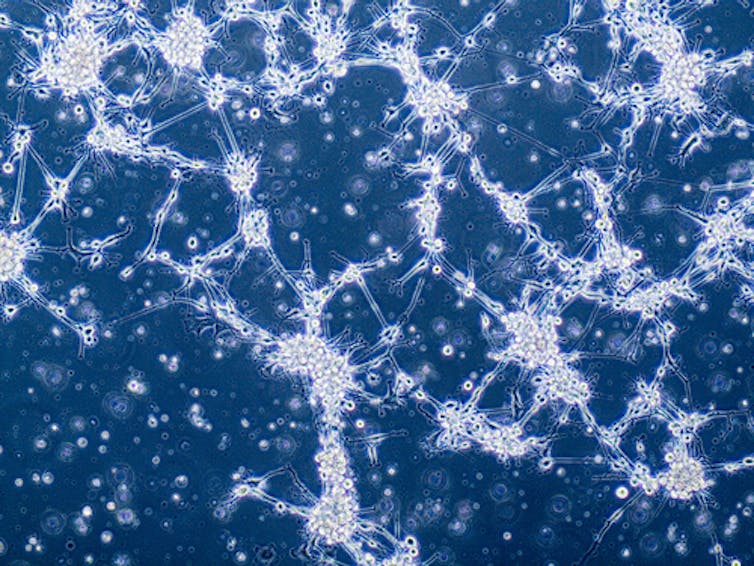

To add to this complexity, we understand now that even within a given patient’s tumor, the individual cancer cells can even differ significantly from one another, having diverged over time through rapid growth and through the accumulation of different mutations within different tumor cells. This means that the same treatment hitting the tumor cells within a single patient will likely not kill all cancer cells with the same effectiveness. This allows resistant tumor cells within the population to grow back in the face of treatment that may have been initially effective.

Tackling this complexity at the cellular level to develop treatments that are effective against all tumor cells within a patient is a major challenge for tumors such as GBM. It likely accounts for much of the resistant nature of the disease.

An additional characteristic of GBM is the invasive nature of the disease. GBM tumor cells essentially crawl away from the main tumor mass and embed themselves deep within the normal brain, often hidden behind a protective barrier known at the blood-brain barrier. This invasive feature means that while neurosurgeons can often remove the main central tumor mass of a GBM, the invasive finger-like projections protrude into other areas of the brain. The distant islands of tumor cells that have migrated away cannot be effectively removed by surgery.